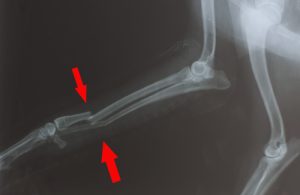

• X-rays or CT scan to assess the type of fracture and plan the treatment options

Broken bones in dogs